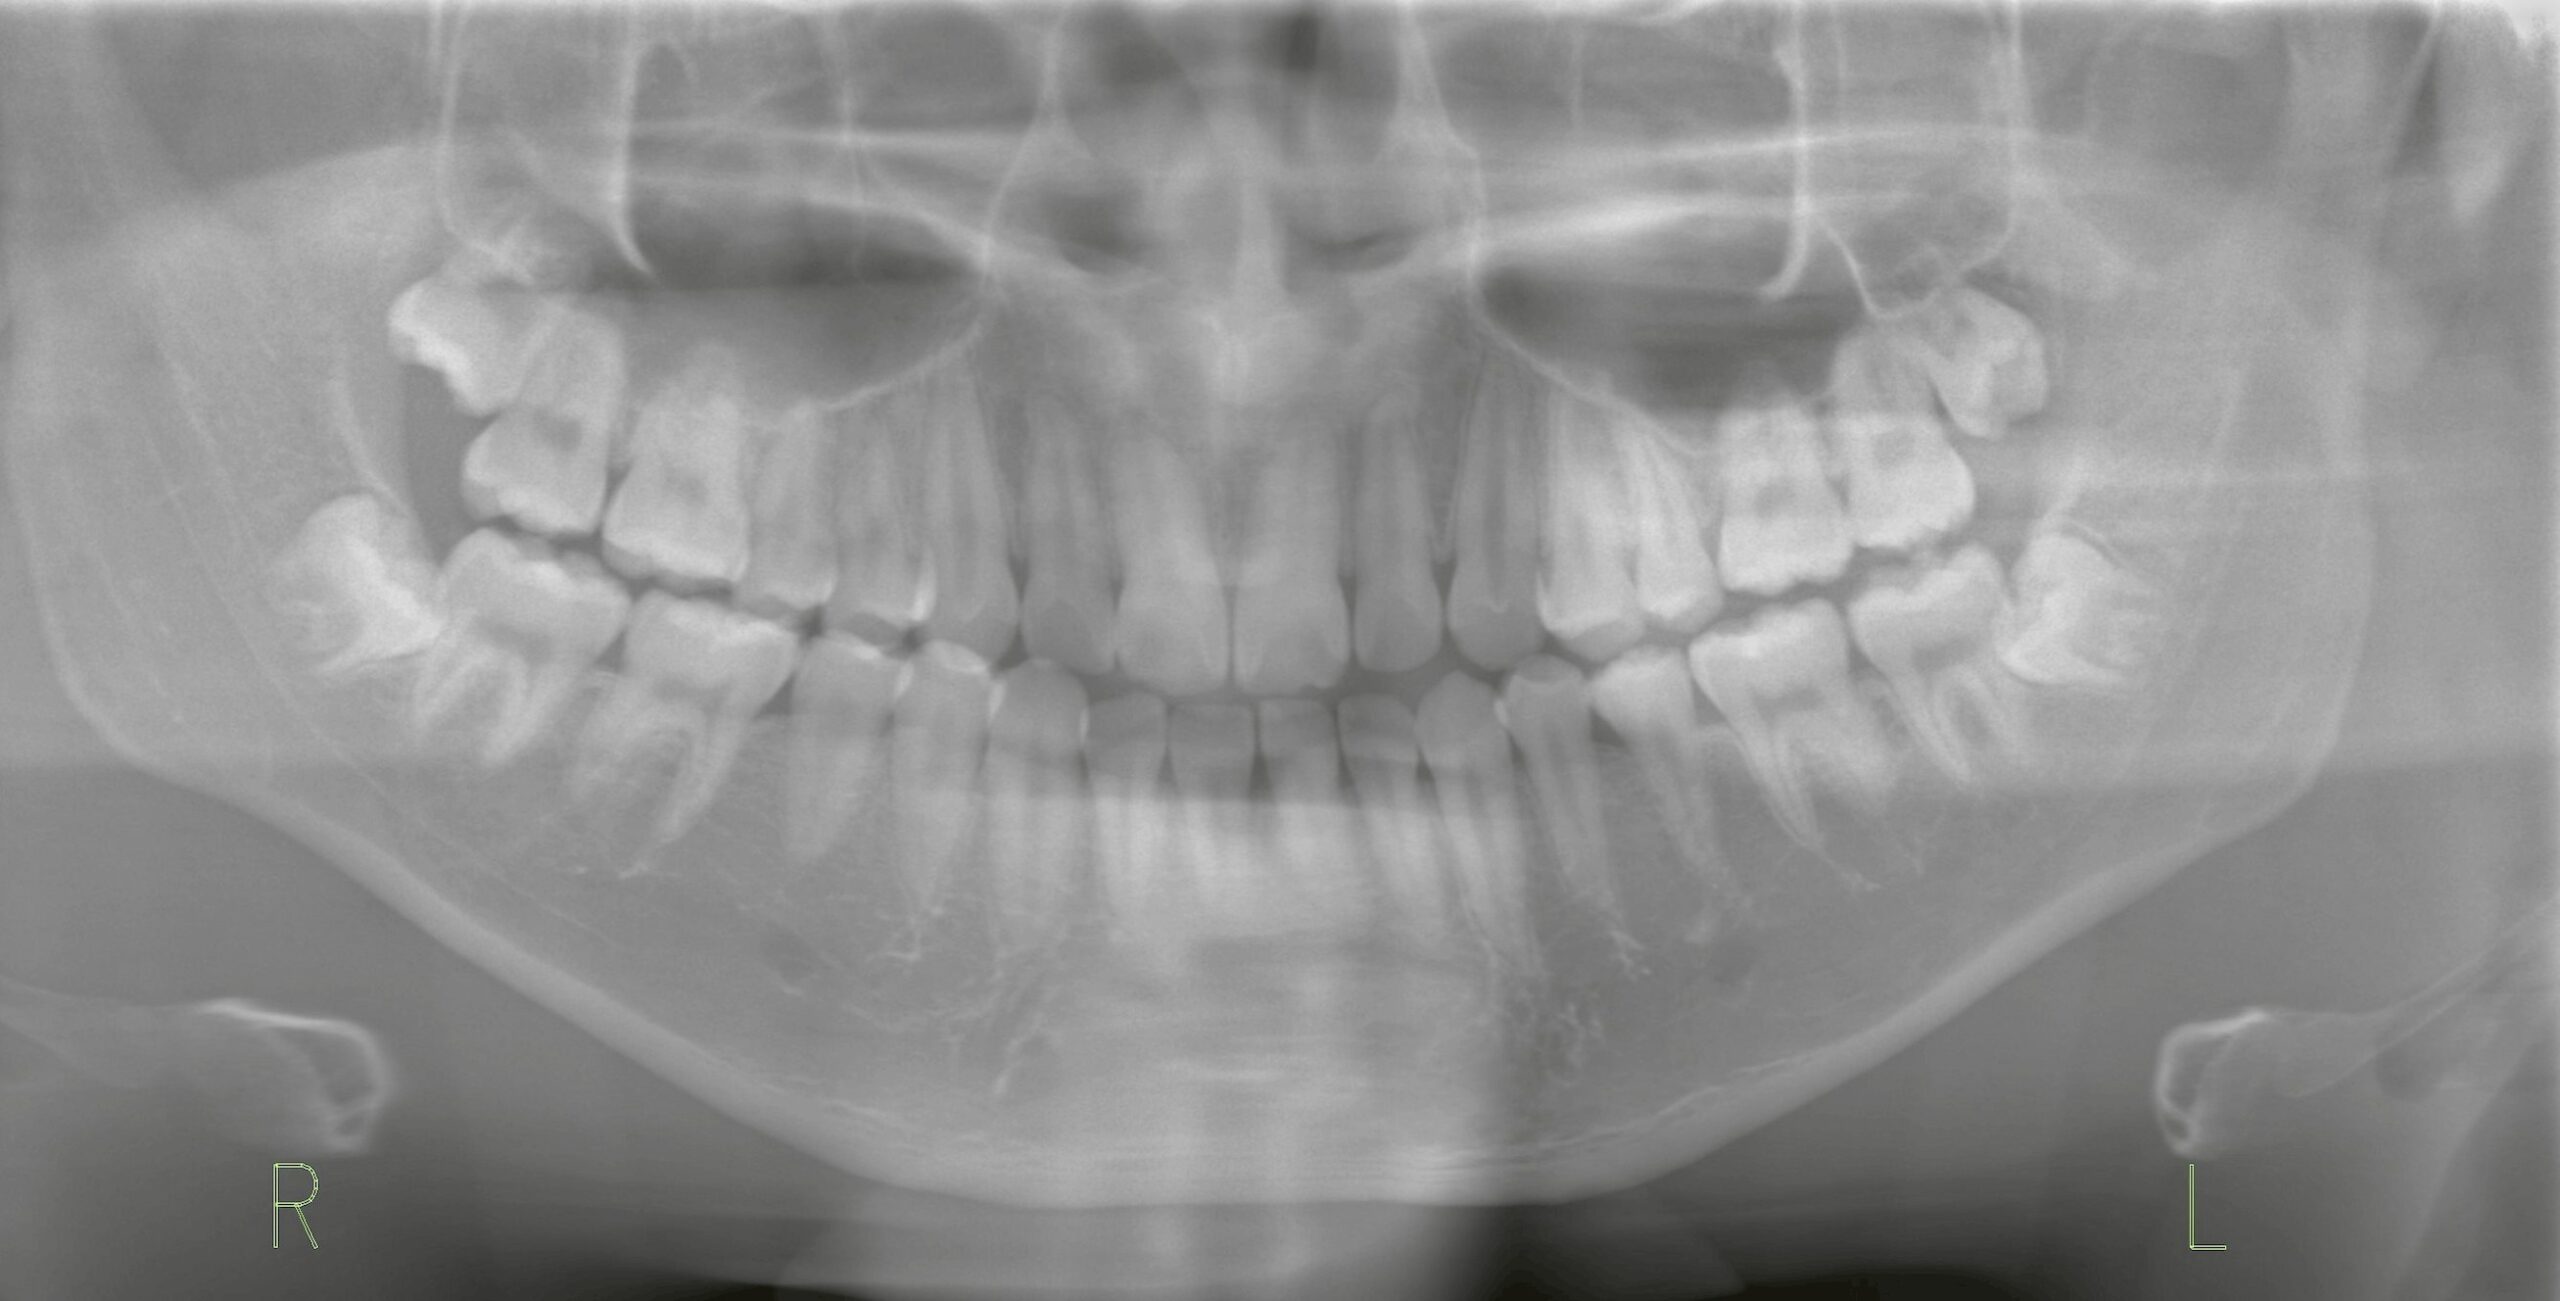

矯正治療を予定している17歳の患者様。

矯正歯科の先生から「上下の親知らずの抜歯」をご依頼いただきました。

一方、下の親知らずはレントゲンで確認すると完全に埋伏しており、歯根がまだ未完成の状態でした。

そのため、17歳前後ではまだ根の形成が途中のことが多く、根が短く先端が細い状態です。

今回は上顎の親知らずは一部切開を行い、下顎の完全埋伏歯については一部骨削除を加えて露出させ、抜歯を実施しました。